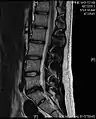

Click images to see larger versions

• Magnetic resonance imaging is the gold standard study for confirming a suspected LDH. With a diagnostic accuracy of 97%, it is the most sensitive study to visualize a herniated disc due to its significant ability in soft tissue visualization. MRI also has higher inter-observer reliability than other imaging modalities. It suggests disc herniation when it shows an increased T2-weighted signal at the posterior 10% of the disc. Degenerative disc diseases have shown a correlation with Modic type 1 changes. When evaluating for postoperative lumbar radiculopathies, the recommendation is that the MRI is performed with contrast unless otherwise contraindicated. MRI is more effective than CT in distinguishing inflammatory, malignant, or inflammatory etiologies of LDH. It is indicated relatively early in the course of evaluation (<8 weeks) when the patient presents with relative indications like significant pain, neurological motor deficits, and cauda equina syndrome. Diffusion tensor imaging is a type of MRI sequence used for detecting microstructural changes in the nerve root. It may be beneficial in understanding the changes that occur after herniated lumbar disc compresses a nerve root, and might help in differentiating the patients that need surgical intervention. In patients with a high suspicion of radiculopathy due to lumbar disc herniation, yet the MRI is equivocal or negative, nerve conduction studies are indicated.[44] T2-weighted images allow for clear visualization of protruded disc material in the spinal canal.